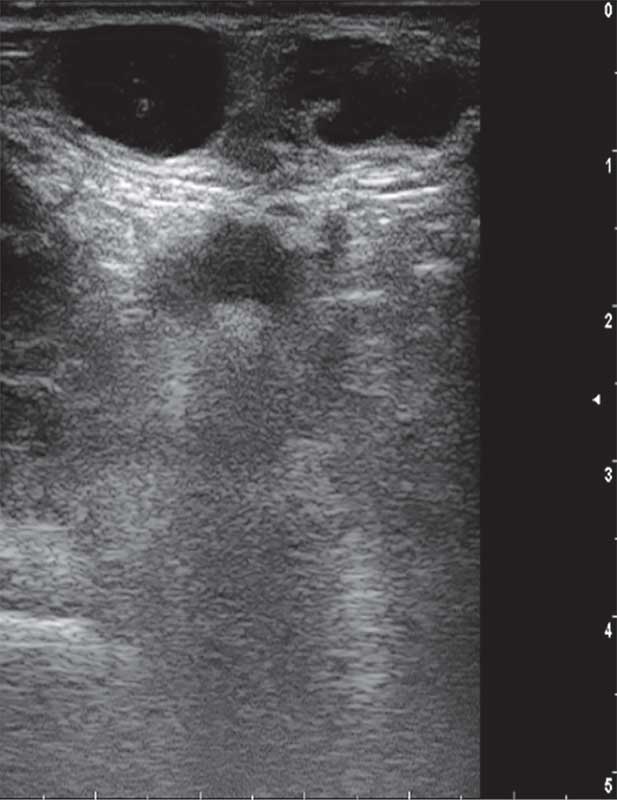

Рис. 4. Ювенильная фиброаденома левой молочной железы у 16-летней девочки

Опухоли подразделяют на доброкачественные и злокачественные [1, 5]. У девочек наиболее распространена ювенильная фиброаденома – доброкачественная фиброэпителиальная опухоль, обычно возникающая в пубертате и склонная к быстрому росту (рис. 2) [5, 11, 12]. Чаще это одиночный узел. Множественные очаги отмечают примерно у каждой пятой пациентки, двусторонние – примерно у каждой десятой [5, 12, 13].

На УЗ-картине солидное, гипоэхогенное по сравнению с тканью МЖ образование однородной структуры, с четкими контурами. Нередко наблюдается дорсальное псевдоусиление без акустической тени (рис. 3–5) [5, 7, 10].